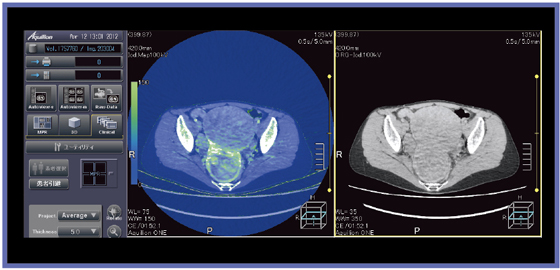

図1にvHPで撮影した当院での症例を示す。患者は胸痛を訴えて来院したため,胸部を心電同期で6秒(HP32),腹部を非同期で4秒(HP91),合計10秒で撮影した。胸部と腹部の境目に段差のない,良好な画像が得られている。また,心電同期撮影を行った胸部はブレやアーチファクトもなく,LADのプラークも明瞭に描出されている。ハーフ再構成のためノイズが多くなるが,AIDR 3Dを使用することで,それが抑えられている。

![]() 図1 vHPを用いた胸腹部の心電同期・非同期撮影 |